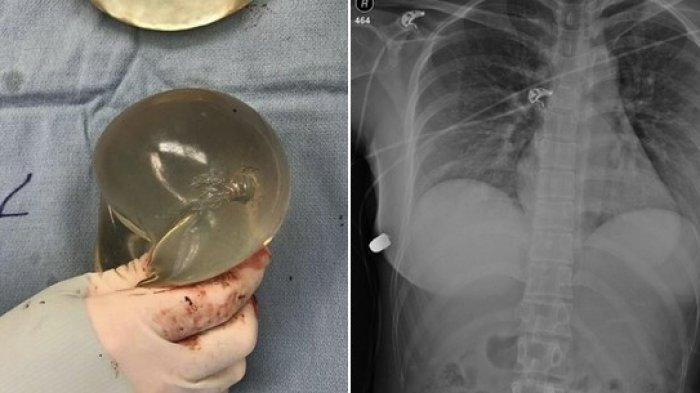

Kisah seorang wanita yang selamat setelah terkena tembakan peluru di bagian dadanya viral di media sosial.

TRIBUNJATENG.COM - Kisah seorang wanita yang selamat setelah terkena tembakan peluru di bagian dadanya viral di media sosial.

Pasalnya, peluru itu ternyata nyangkut di implan payudara miliknya sehingga tak tembus ke organ dalam.

Dalam unggahannya, akun itu membagikan potret sebuah peluru yang bersarang di dalam implan payudara tranparan.

Kemudian dalam foto berikutnya terlihat hasil Rontgen milik korban.

Tampak peluru kecil itu menembus bagian depan dada.

Kasus ini sendiri pertama kali diungkap oleh Sage Journal pada 15 April 2020.

Dalam artikel itu dituliskan jika korban penembakan adalah seorang wanita berusia 30 tahun.

"Seorang wanita berusia 30 tahun dengan riwayat implan payudara silikon subpektoral ditempatkan melalui sayatan periareolar (bulat halus 450 mL) dilihat oleh layanan trauma untuk evaluasi trauma tembus dada akibat luka tembak,"